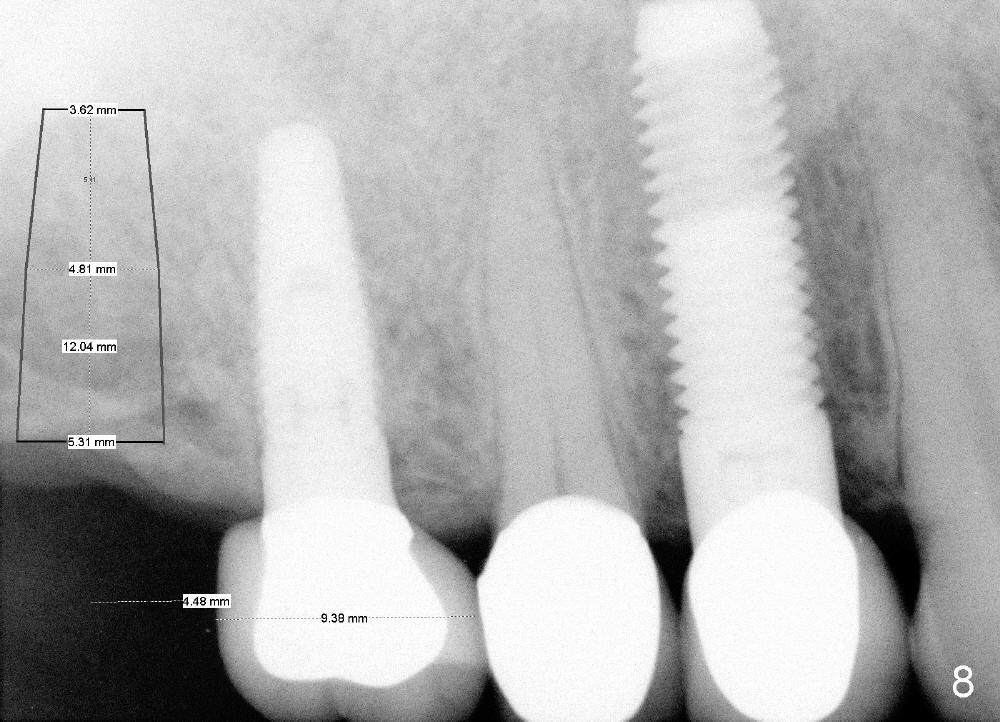

Further search of the patient's files finds X-ray taken prior to #5 extraction (Fig.7). Bone height is estimated 12 mm. Since the mesiodistal width of the 1st molar is less than 10 mm (Fig.8), the center of the osteotomy at the site of #2 should be 4.5 mm (3.5 mm from the 2 mm pilot drill). If the bone allows, 5.3x12 implant will be placed.